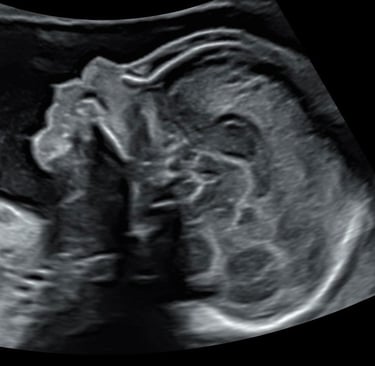

Lors d’une grossesse, l’échographie est un outil indispensable pour le suivi.

Il s’agit d’un examen de dépistage et non d’un diagnostic.